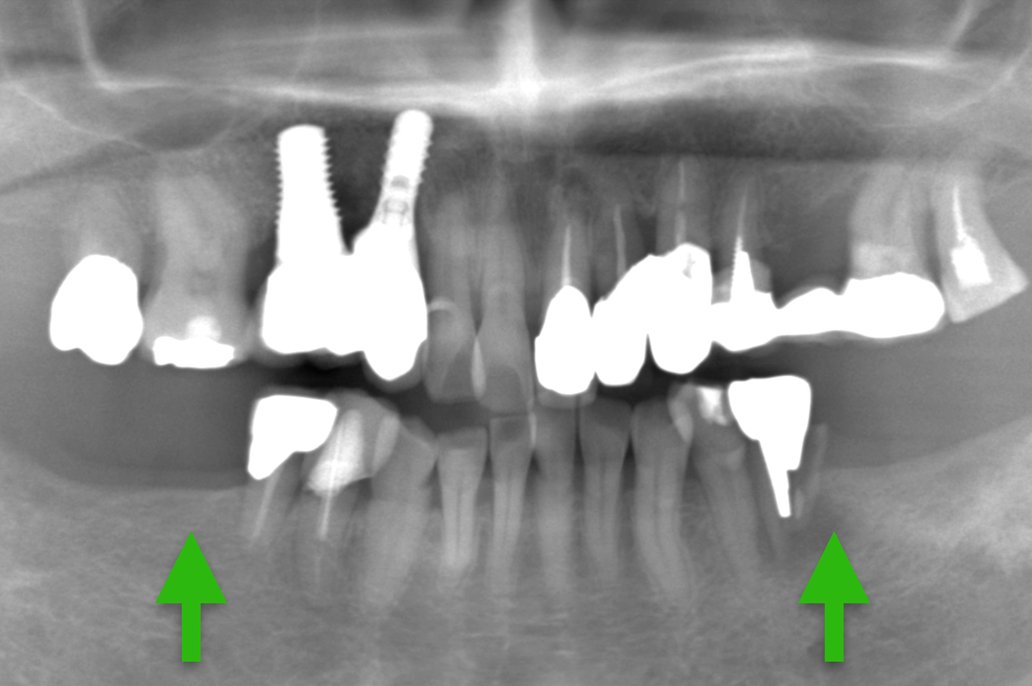

| 主 訴 | 左下が噛むと激痛 |

|---|---|

| 治療期間 | 約4ヶ月 |

| 治療費 | 合計957,000円(税込) |

| 治療内容 | 治療1回目 保存不可能な歯の抜歯 治療2回目 CT撮影にて顎の骨にインプラントが入ることを確認し、サージカルガイドの型取り 治療3回目 インプラントを入れる治療 治療4回目 縫合してある糸をとり、周りをクリーニング 治療5回目 インプラントに土台を立てる治療 治療6回目 上部構造(被せ物)の型取り 治療7回目 上部構造(被せ物)をセット |

| 治療のリスク | インプラントの手術の後は腫れ、 痛みが出ることがあり ます。 |